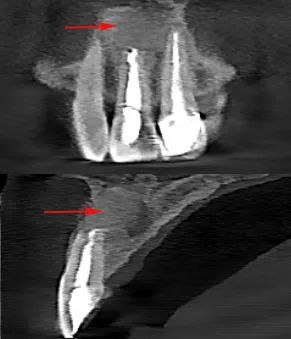

术后3个月复查

术后3个月CBCT图像

根尖囊肿的治疗视囊肿的大小及累及范围而定,如果囊肿较小,多采用保守治疗,通过常规根管治疗消除感染源,部分囊肿经过完善的根管治疗后即可自行痊愈。如果囊肿较大,已侵犯多颗邻牙,或经过根管治疗,定期复查后发现囊肿仍未消失或没有缩小的迹象,则需通过外科手术处理。手术过程中,医生会将囊肿区域的牙龈翻开,暴露囊肿,将其完全摘除,并切除根尖部分牙根,使用生物陶瓷材料回填,封闭根尖,植入骨粉,覆盖骨膜,随着时间的推移,新生骨质会逐渐长入囊肿所在部位,使病变愈合。病灶牙和被囊肿累及而无法保留的牙齿,也可在手术同期一并拔除。